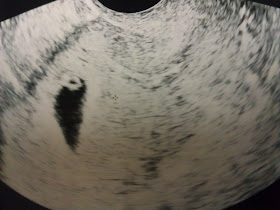

As many of you know we had our ultrasound a few days ago.

Here is what we saw.

Yep, 1 teeny tiny beating heart!

At 6 weeks 3 days along Baby L was growing well & had a heartbeat of

124 bpm!

The ultrasound was so cool and getting to hear the heartbeat was amazing! The doctor at ohsu told us that if we couldn't get into our new OB between 8 & 9 weeks along that we could come back to ohsu for another ultrasound. So, we will get to go back on the 12th (8 weeks 3 days)for another peek at our baby and then the 25th we will get to meet our OB for the first time and hopefully get another look at our growing baby!

right now you are 6 weeks and 6 days along(almost 7 weeks! woohoo!) and growing great in your Aunt Holly's belly. This week you are about the size of a blueberry and are 10,000 times bigger then you were when you first started growing! You're currently making Aunt Holly a very tired lady, especially when she has to chase your crazy cousin around! Every once in a while you make her bit nauseous too! Mommy thinks that's great though because it means your growing big and strong. Keep growing little one!